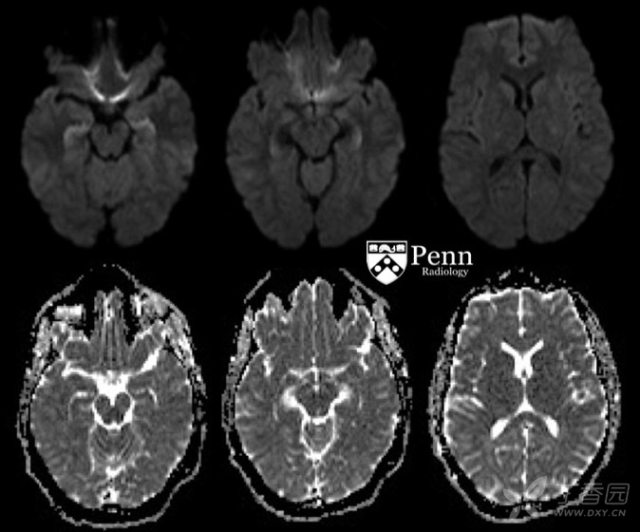

为了明确诊断,对患者进行了头颅 MRI 检查。颅脑轴位 T2-FLAIR、DWI、ADC 及 GRE MR 图像如下:

颅脑 MRI 显示双侧海马可见对称性 FLAIR 高信号及扩散受限。未见明显出血征象、占位效应或脑积水征象。未见明显特异性征象,可能是由于近期癫痫导致的。尽管缺氧缺血性脑病也可累及海马,但脑实质中无足够的证据支持缺氧缺血性脑病。

大脑不同的区域都可受累,包括海马(最为常见,约为 50% 病例可见)、丘脑(多见于丘脑后结节区域)、基底节、大脑皮层、皮层下白质和胼胝体。

MRI 上,常见表现为在受累区域出现 T2/FLAIR 异常高信号,通常这些表现是可逆的。

在受累区域也有可能出现 DWI 高信号,有时合并 ADC 低信号,这多提示为永久性损伤,有时尽管也是可逆的。

约有 50% 的病例病变是双侧的。